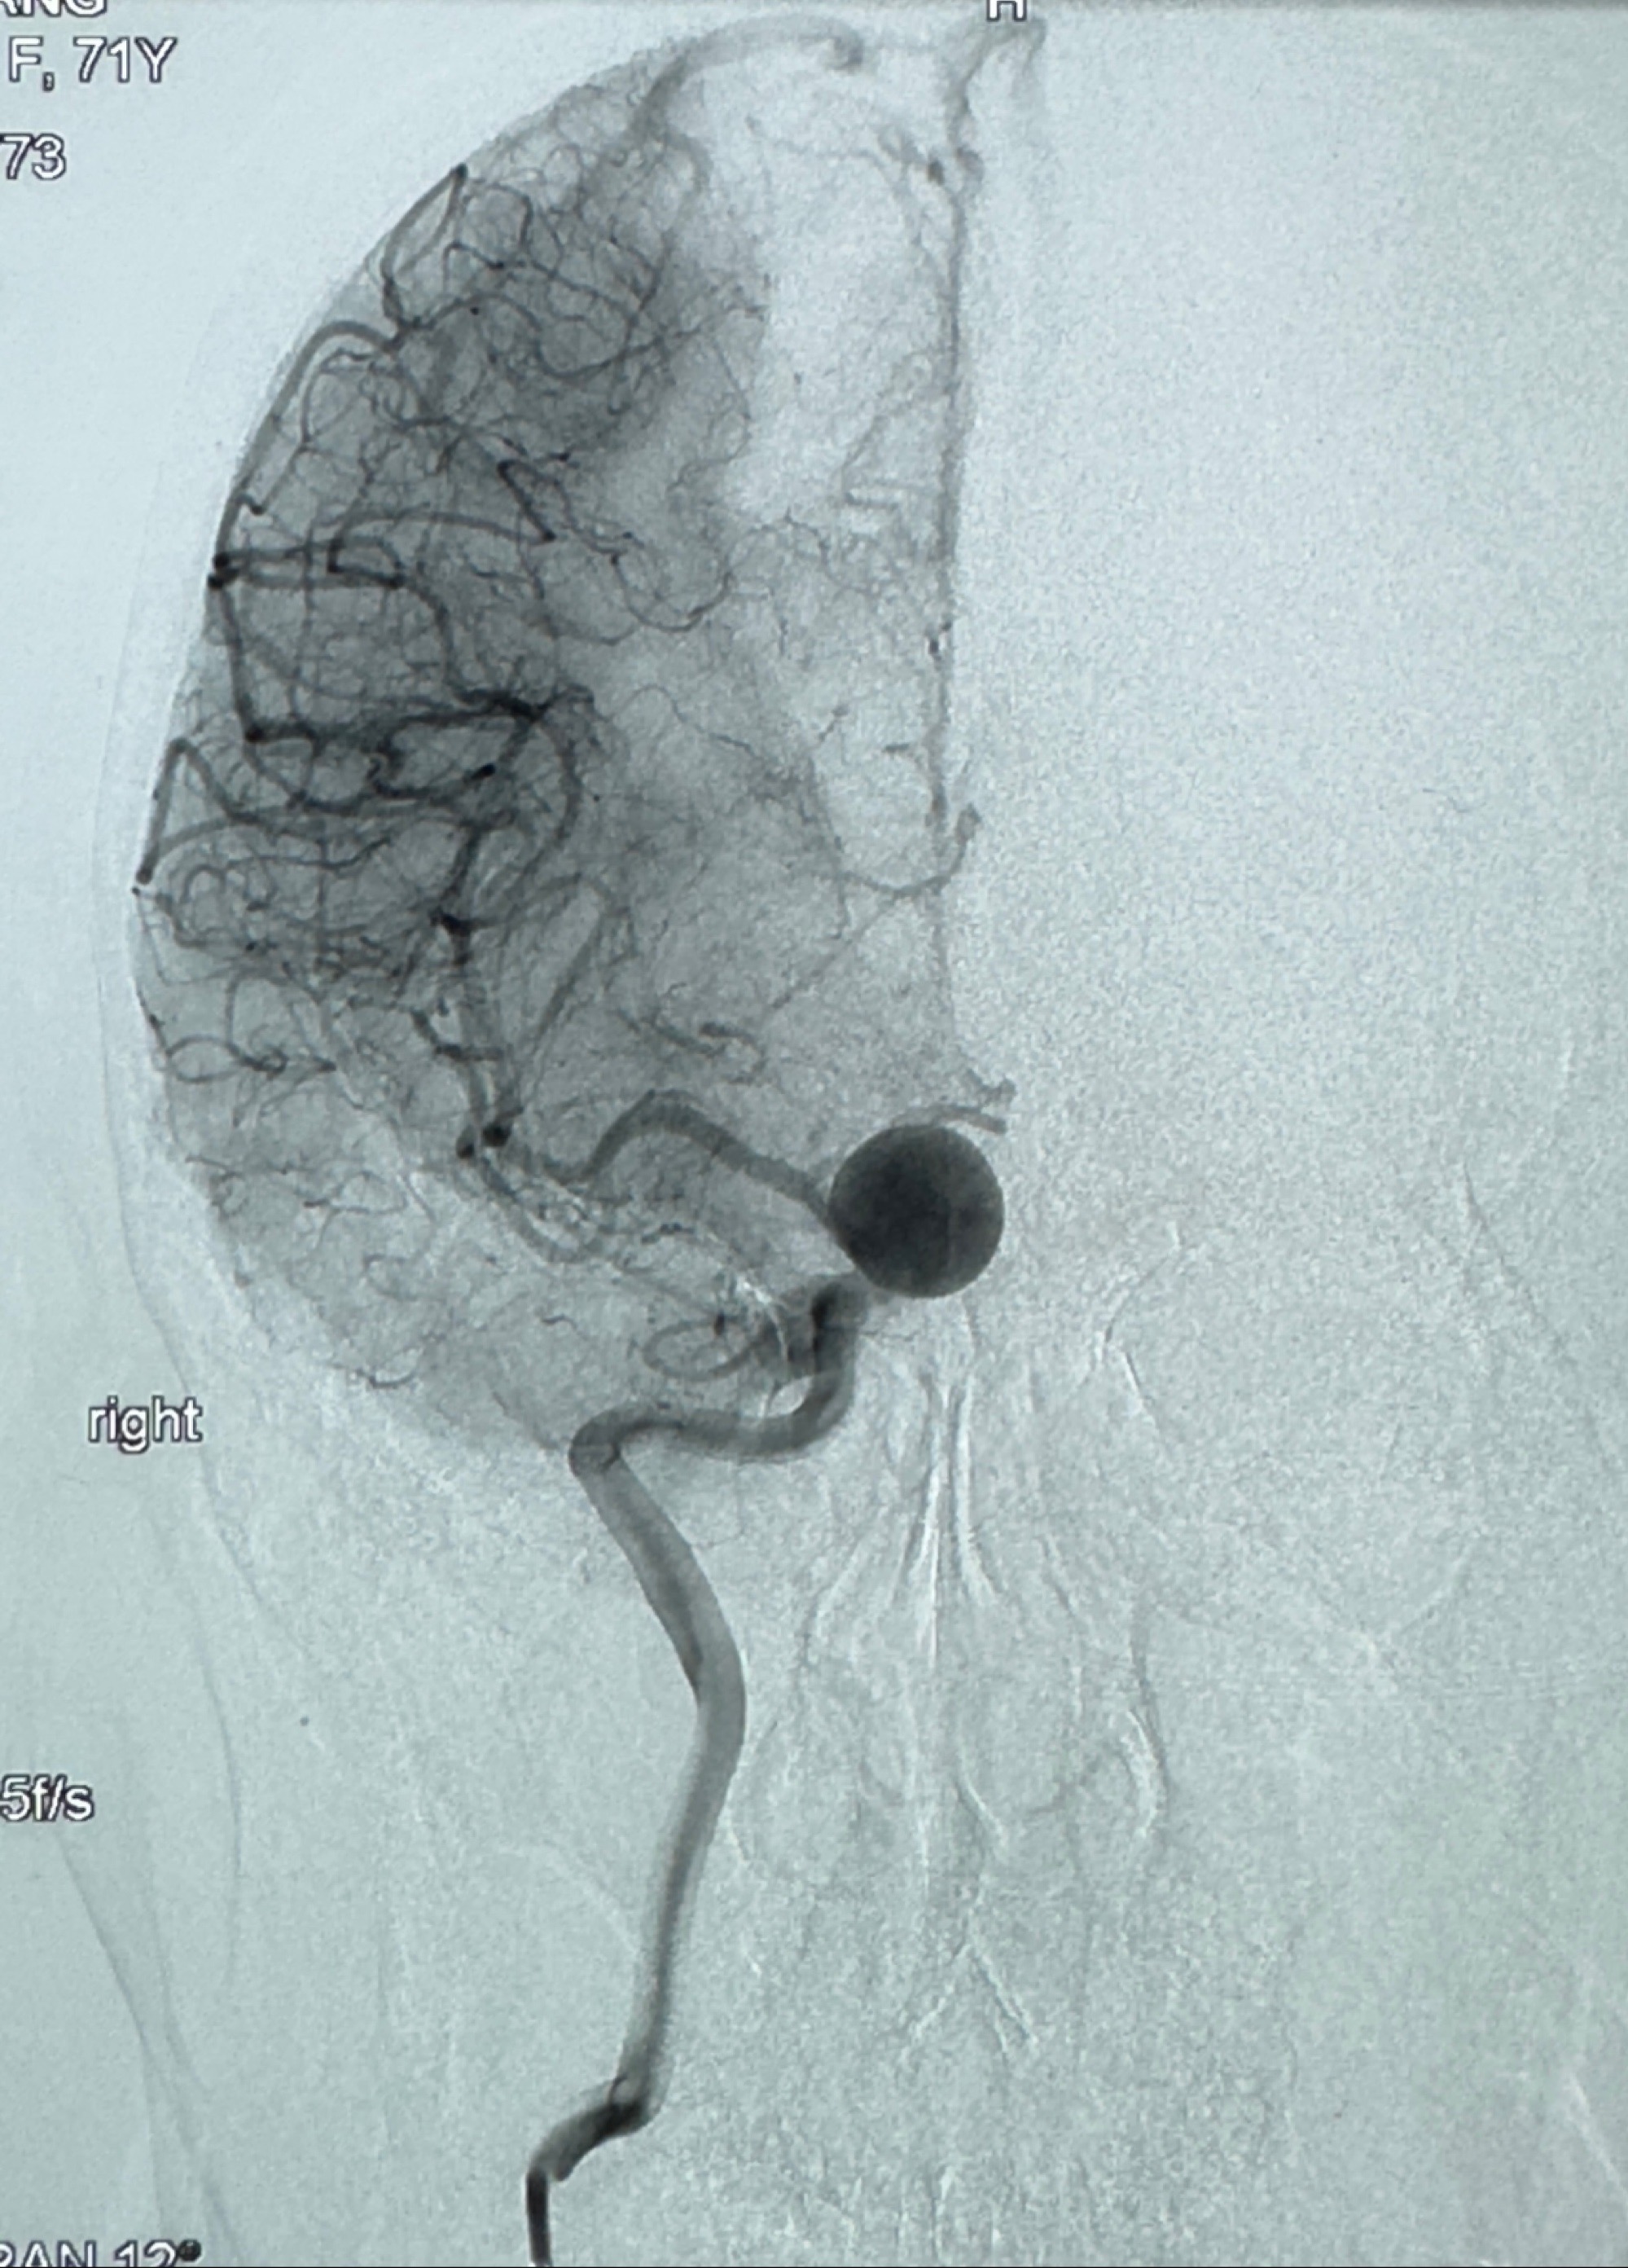

2023-12-27术后第十天复查DSA

支架贴壁佳,但可见射流,咋办?

2024-01-08全麻下再行植入密网支架一枚

Tubridge 4.5-35mm

支架植入顺利,贴壁佳,支架内血流通畅,动脉瘤内血液滞留明显